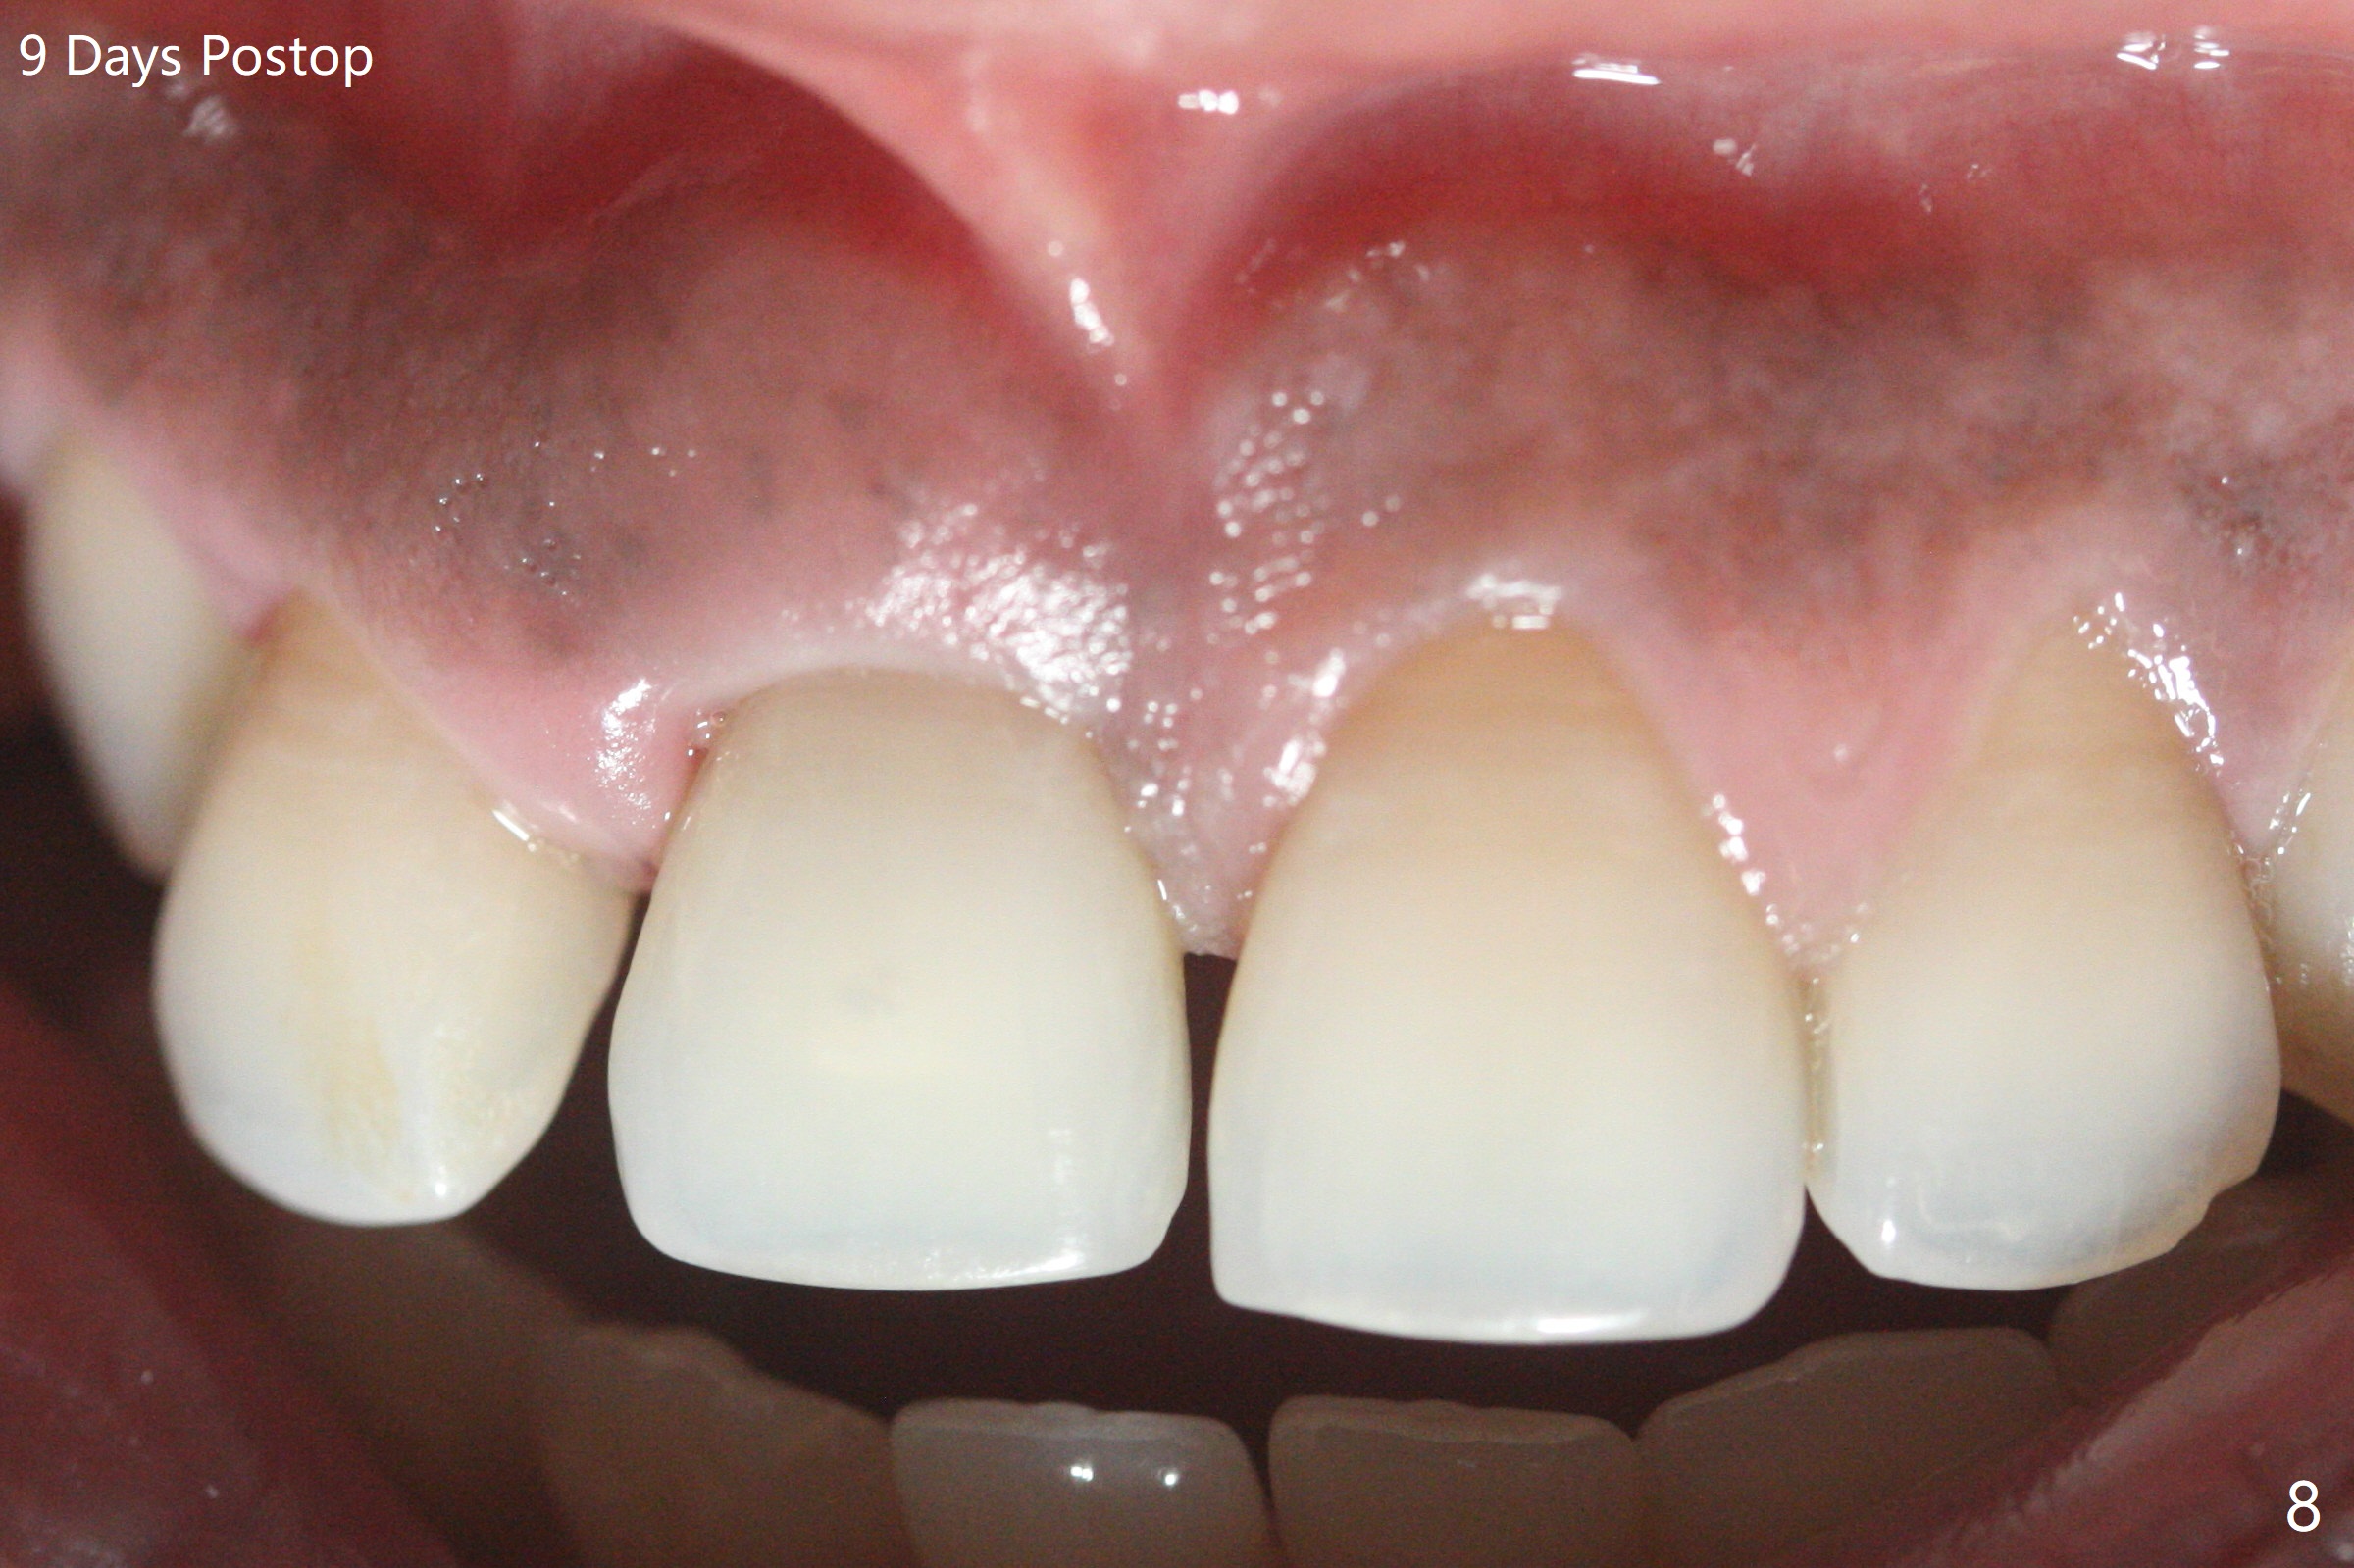

50岁女8号牙远中颊侧冠方移位(图一),牙根暴露(*),前磨牙-前磨牙开合,腭侧牙龈红肿。拔除清创后,使用导板钻洞,徒手植入2.5x13毫米一段式植体,首先将PRF膜插入腭侧,剩余牙槽窝空间植入粘性骨粉(图二:*)。截断拔除牙齿,牙冠掏空,反复调整牙冠长度,使用流动性树脂(flowable composite,图三:*)衬里固定牙冠(C),恰好PRF封闭远中颊侧牙槽窝开口(图四),自然牙冠和一段式植体配合,形成最佳emergency profile,最后牙周敷料进一步封闭牙槽窝(图五),防止骨粉早期脱落,不必担忧敷料不透气。腭侧牙龈红肿(图六)。服用Augmentin两天,患处没有触痛了(图七)。术后九天颊侧牙龈继续延长(图八).